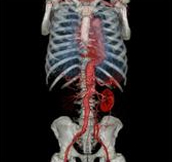

Body angiography with automatic bone and table removal - MIP reconstruction. Case: Aortic dissection. Left common iliac artery occlusion. Scanning: P0.83, 0.5s, 360mA, 100kV, weight 80kg, contrast 80cc